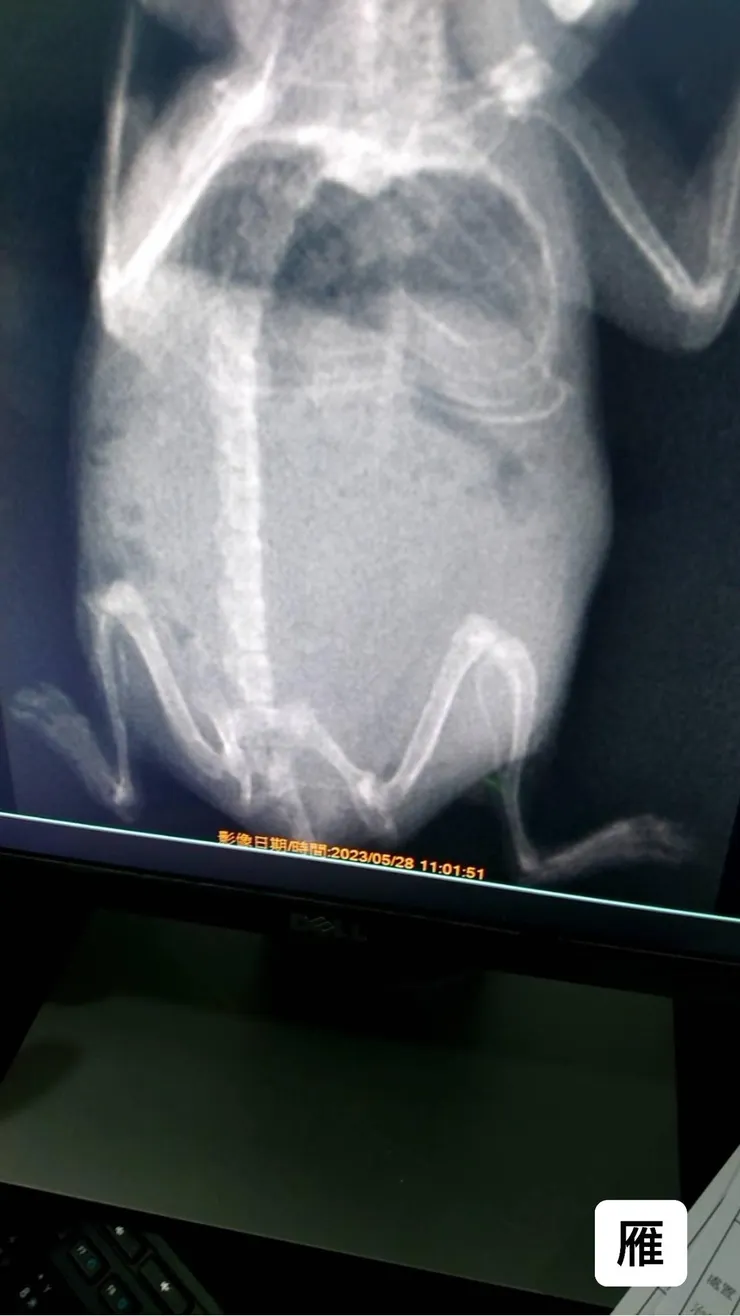

經觸診發現異常,故照X光先確定裡面是否為腹水或脹氣,X光圖片呈現出來經判定懷疑子宮蓄膿,有團塊推擠到臟器,

若高度懷疑子宮蓄膿情況下,飼主欲採積極治療可直接開腹探查並做團塊摘除動作,若非積極治療則採吃藥療程,提供雁短時間內生活品質,

5/29早晨中途將雁送至醫院,下午執刀約一小時後中途接到電話告知非子宮蓄膿而是脾臟腫瘤,詢問中途是否摘除,風險較高,有機率大出血導致過往,不摘立即縫合則醒來後採安寧治療,考量雁的生活品質,最終經決策採摘除手術,約莫傍晚醫師致電告知雁已清醒並開始活動,手術順利完成。